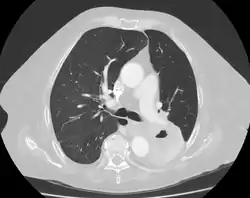

Diagnosis of a lung cavity is made with a chest X-ray or CT scan of the chest,[2] which helps to exclude mimics like lung cysts, emphysema, bullae, and cystic bronchiectasis.[5] Once an imaging diagnosis has been made, a person’s symptoms can be used to further narrow the differential diagnosis. For example, recent onset of fever and productive cough suggest an infection, while a chronic cough, fatigue, and unintentional weight loss suggest cancer or tuberculosis.[2] Symptoms of a lung cavity due to infection can include fever, chills, and cough.[5] Knowing how long someone has had symptoms for or how long a cavity has been present on imaging can also help to narrow down the diagnosis. If symptoms or imaging findings have been present for less than three months, the cause is most likely an acute infection; if they have been present for more than three months, the cause is most likely a chronic infection, cancer, or an autoimmune disease.[5]